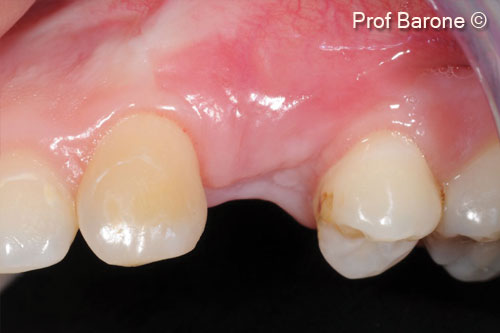

Tình hình ban đầu

Một bệnh nhân nữ (27 tuổi) có biểu hiện nhiễm trùng cấp tính và mủ từ lỗ rò ở miệng.